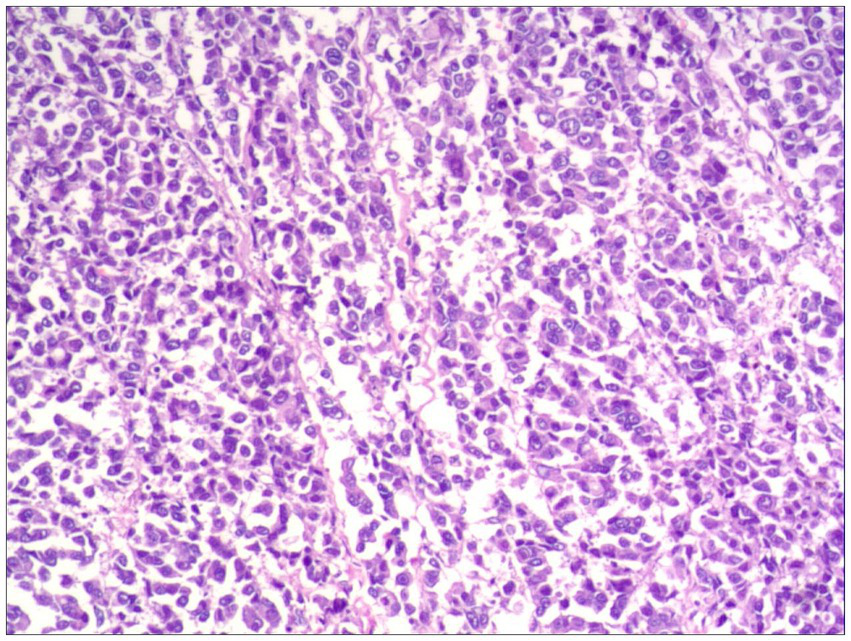

Histopathological examination confirmed R0 resection in all cases, featuring epithelioid or spindled neoplastic cells with nuclear pleomorphism (enlargement, hyperchromasia, prominent nucleoli) and abundant eosinophilic to granular cytoplasm. Tumors exhibited infiltrative growth patterns into smooth muscle and fibrous septa, with associated focal melanin deposition and adjacent mucosal necrosis (Figure 2).

Figure 2

Focal melanin deposition (H&E, ×100).